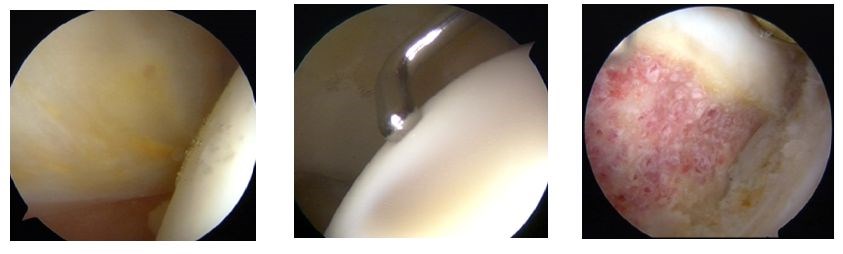

Alle oorzaken van young adult hip problems weergegeven in punt 1 en 2 kunnen worden aangepakt met een arthroscopie van de heup.

Heuparthroscopie is een krachtig instrument geworden. Waar vroeger grote incisies moesten worden gemaakt om iets te kunnen doen aan de heup, kan dat nu via 3 tot 5 kijk- en werkgaatjes. Daarmee kunnen we in het heupgewricht en over de hals van het femur kijken. Het biedt ons bovendien de mogelijkheid de slijmbeurs en het posterieure kapsel rond de heup te bekijken. De ingreep gebeurt in het dagziekenhuis onder algemene narcose. Na de ingreep moeten onze patiënten 4 weken met krukken stappen waarbij ze toch volledig mogen steunen. Kinesitherapie wordt ten vroegste op 4 weken gestart. Na 3 weken mag worden gefietst, na twee maanden gejogd en na 6 maanden mogen alle activiteiten worden hervat.